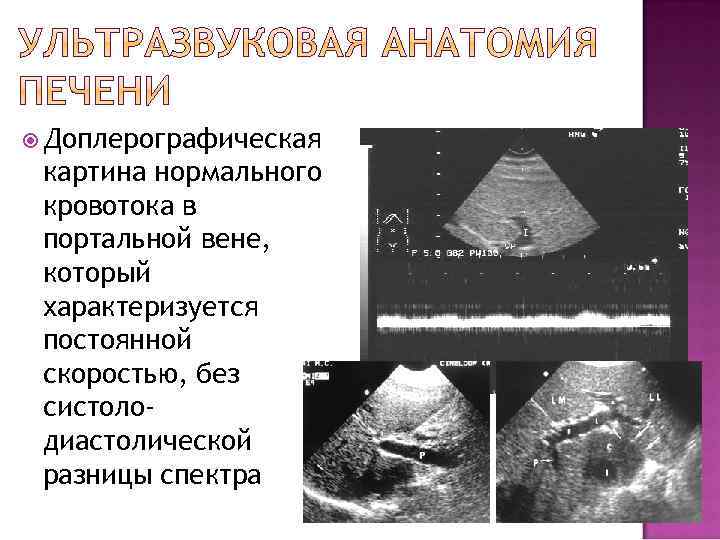

Доплерографическая картина нормального кровотока в портальной вене, который характеризуется постоянной скоростью, без систолодиастолической разницы спектра